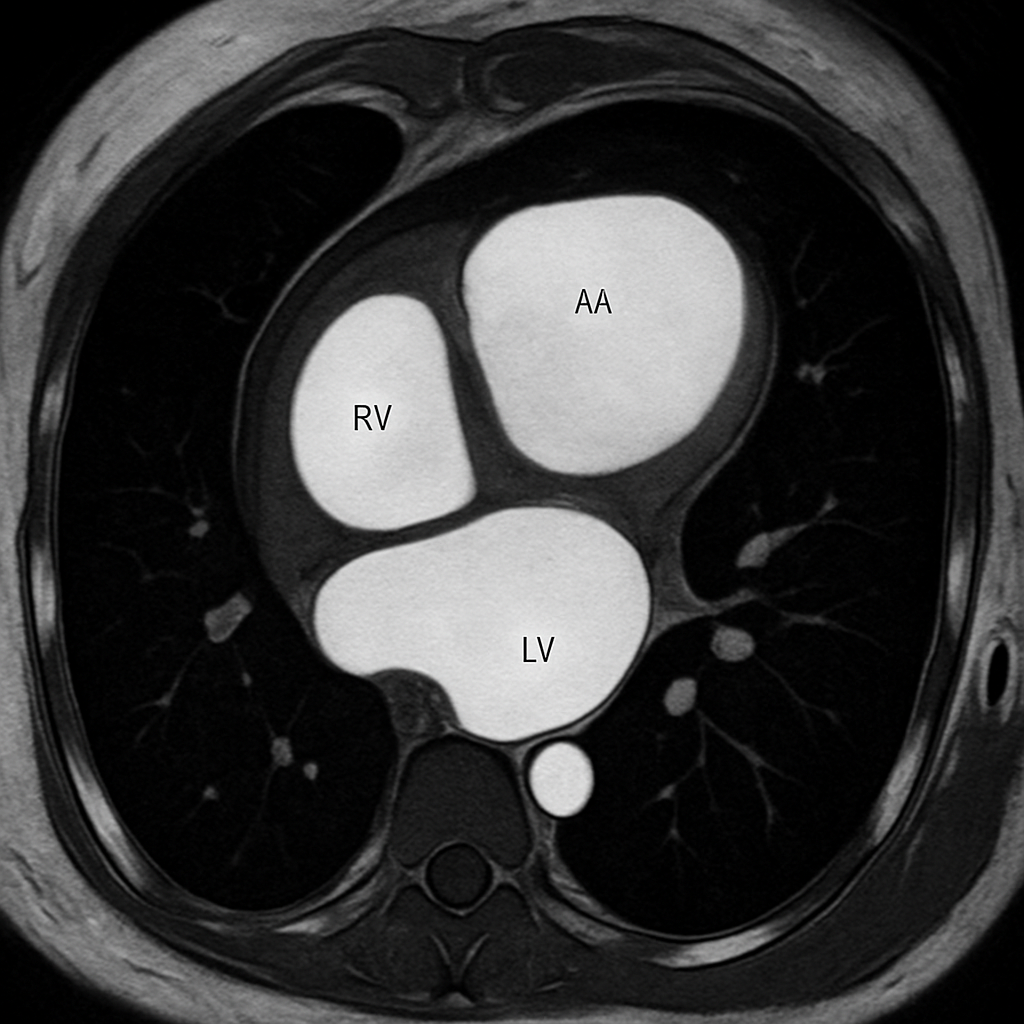

CT — Axial Non-Contrast

Axial non-contrast CT of the heart showing all four chambers, myocardium, pericardium, and coronary artery calcifications. Soft tissue window.

CT AI Generated 2026-03-16

Axial Non Contrast 5 mm 120 kVp W:400 L:

Non-contrast cardiac CT for calcium scoring; show LAD, LCx, RCA calcifications